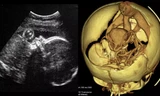

Các bác sĩ ghi nhận bệnh nhân bị 1 thanh sắt đâm từ bả vai xuống hông, 1 thanh đâm thủng vai từ trước ra sau; tình trạng hô hấp yếu dần. Bệnh nhân được hồi sức, giảm đau, siêu âm, chụp X-quang tại khoa cấp cứu.

Bệnh viện đã huy động các y bác sĩ hội chẩn và tiến hành mổ suốt 2 tiếng đồng hồ để rút 2 thanh sắt ra khỏi cơ thể, xử lý các vết thương.

Qua phẫu thuật, kíp mổ do bác sĩ Huỳnh Quốc Khởi (Trưởng khoa Ung bướu) phụ trách, ghi nhận anh Q. có vết thủng phổi, thủng cơ hoành và thủng gan.